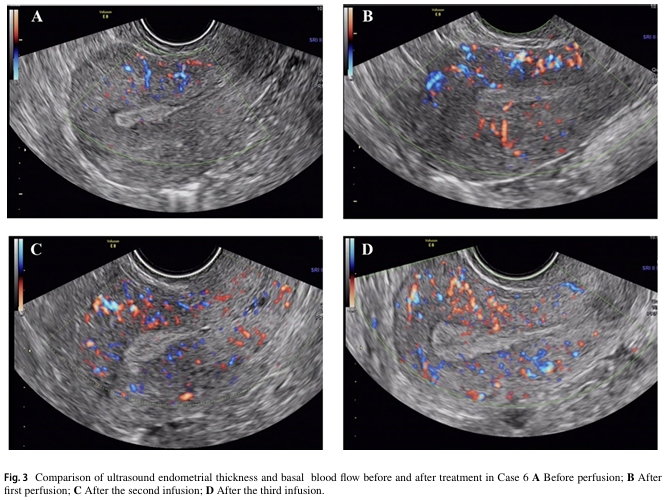

七名患者在術(shù)后進行三次自體骨髓間充質(zhì)干細胞宮腔灌注治療。兩年內(nèi)進行隨訪,子宮內(nèi)膜厚度和基底層血流量均有明顯改善,宮腔內(nèi)形態(tài)正常,且均未檢查到新的宮腔粘連癥狀。其中兩例患者在術(shù)后分別經(jīng)自然受孕和胚胎移植成功分娩。